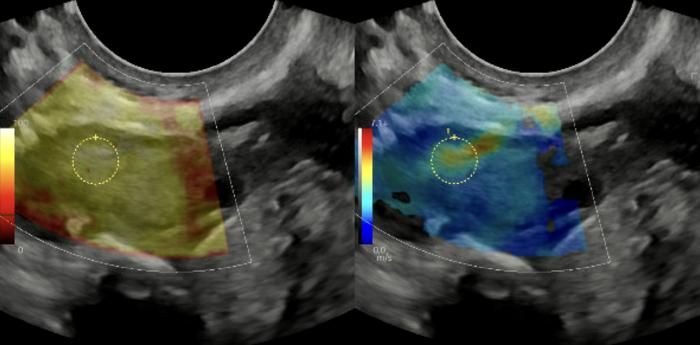

In a previous study , Duncan’s lab was the first to find that as ovaries age, they become excessively inflamed, fibrotic and stiff — similar to scarring in other tissues. Because cancer cells prefer collagen-rich, stiff environments, aged ovaries provide suitable conditions for cancer cells to proliferate, Duncan said.

Stiff ovaries also affect egg quality, the earlier study found, which could help explain why women’s fertility declines in their 30s and 40s.